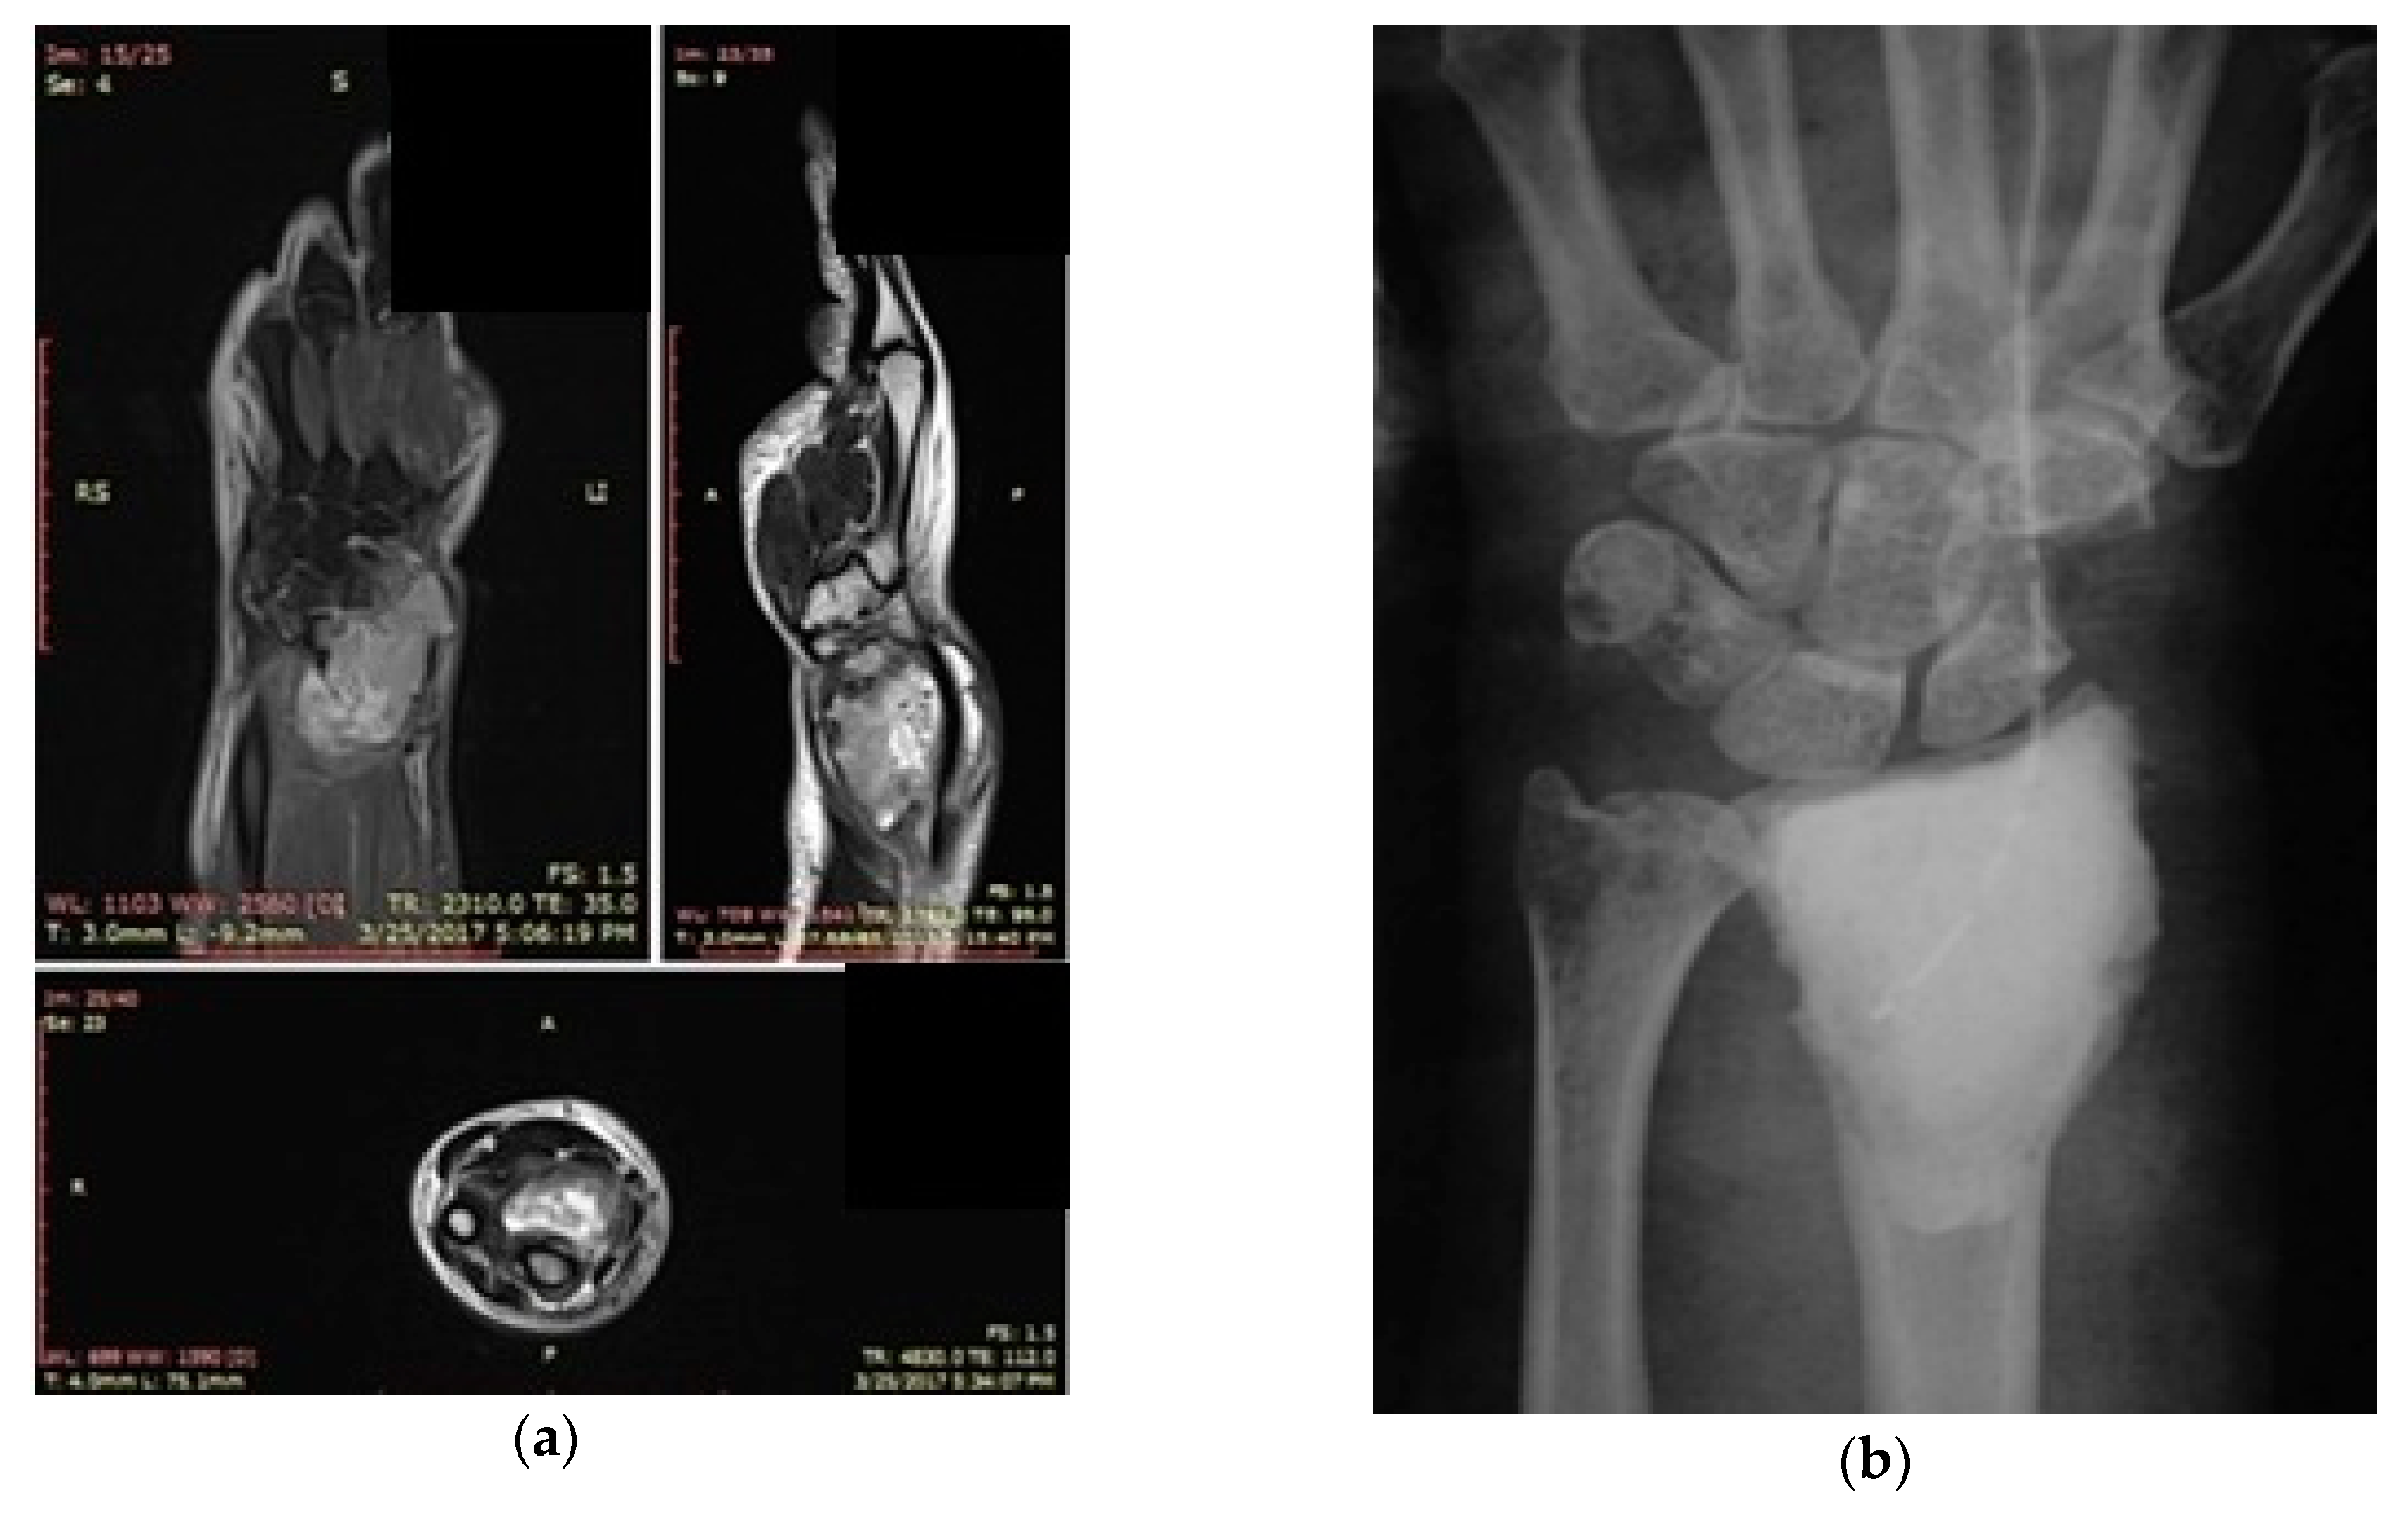

3.2. Case 2